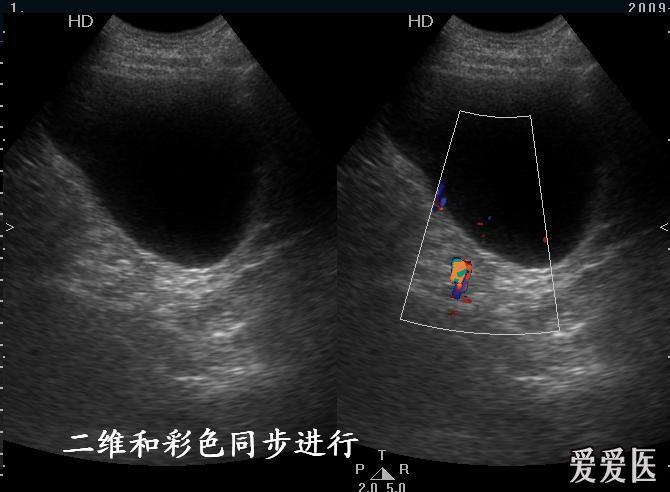

输尿管超声手法图解,输尿管扩张超声图片

输尿管扩张超声图片

输尿管超声分段解剖图

超声图像